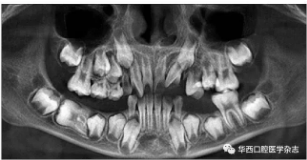

全景片及錐形束CT(cone beam computed tomo-graphy,CBCT)三維重建影像顯示:46牙胚存在,牙冠朝向遠中,且牙長軸與下頜骨下緣接近平行,遠中根發育約為根長2/3,近中根發育約為根長1/2且稍向下彎曲,近中根與45牙關系密切,下頜其余牙胚正常(圖2、圖3)。